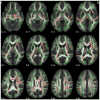

Children born preterm are at risk for deficits in language and reading. They are also at risk for injury to the white matter of the brain. The goal of this study was to determine whether performance in language and reading skills would be associated with white matter properties in children born preterm and full-term. Children born before 36 weeks gestation (n=23, mean±SD age 12.5±2.0 years, gestational age 28.7±2.5 weeks, birth weight 1184±431 g) and controls born after 37 weeks gestation (n=19, 13.1±2.1 years, 39.3±1.0 weeks, 3178±413 g) underwent a battery of language and reading tests. Diffusion tensor imaging (DTI) scans were processed using tract-based spatial statistics to generate a core white matter skeleton that was anatomically comparable across participants. Fractional anisotropy (FA) was the diffusion property used in analyses. In the full-term group, no regions of the whole FA-skeleton were associated with language and reading. In the preterm group, regions of the FA-skeleton were significantly associated with verbal IQ, linguistic processing speed, syntactic comprehension, and decoding. Combined, the regions formed a composite map of 22 clusters on 15 tracts in both hemispheres and in the ventral and dorsal streams. ROI analyses in the preterm group found that several of these regions also showed positive associations with receptive vocabulary, verbal memory, and reading comprehension. Some of the same regions showed weak negative correlations within the full-term group. Exploratory multiple regression in the preterm group found that specific white matter pathways were related to different aspects of language processing and reading, accounting for 27-44% of the variance. The findings suggest that higher performance in language and reading in a group of preterm but not full-term children is associated with higher fractional anisotropy of a bilateral and distributed white matter network.